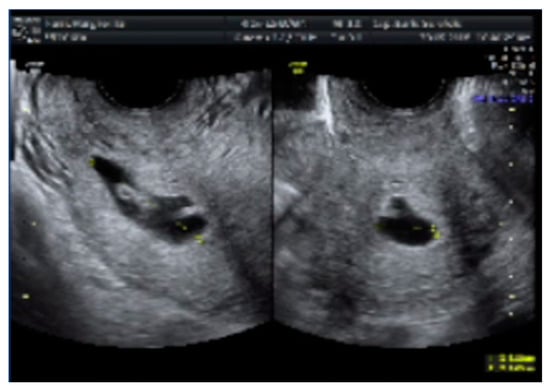

- Case 1. Hysteroscopy was performed in two steps. During the first phase a 5 mm Bettocchi hysteroscope (Storz®, Karl Storz SE & Co, Tuttlingen, Germany) with 5 Fr bipolar electrode Versapoint Twizzle (Gynecare®) was used to identify the GS: it was opened and the pregnancy terminated by cord section and vessels were partially coagulated; subsequently, the cervix was dilated and we performed a resectoscopy. During the second phase the GS and the embryo were removed and a 10 mm resectoscope with bipolar Versapoint (Gynecare®) was used to obtain a complete resection of the residual chorial villi. Lastly, we performed an electrocoagulation of the bleeding vessels on implantation site, in order to control the hemostasis (Figure 1, Figure 2, Figure 3 and Figure 4)